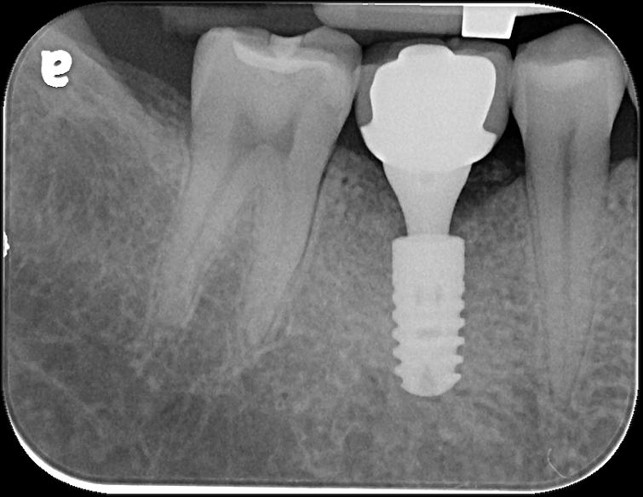

治療前,牙骨已破壞

植牙後,角度良好